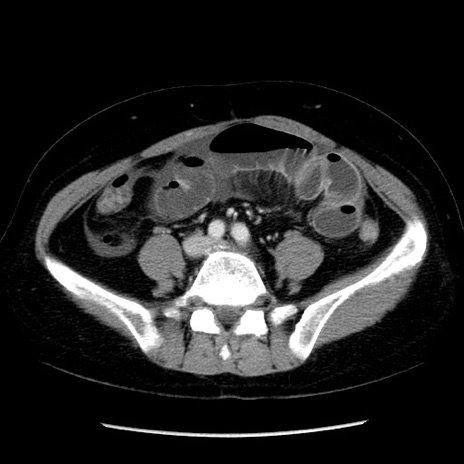

症例6(横断像)

【症例】50歳代女性

【主訴】下腹部痛

【現病歴】本日朝より下痢2回あり。 昼食を食べた後、嘔吐3回、下腹部痛認め、症状軽快せず、当院救急搬送。

最終食事:本日昼(生ものなし)。 昨日の夜、刺身を食ぺたとのこと。周囲に同様の症状の者なし。普段、排便は毎日あるとのこと。

【既往歴】卵巣癌術後(8年前に当院で卵巣摘出)

【身体所見】 意識清明、腹部:平坦、腸蠕動音→、やや硬、下腹部自発痛・圧痛あり、反跳痛あり、筋性防御なし。

【データ】WBC 16000、CRP 0.01